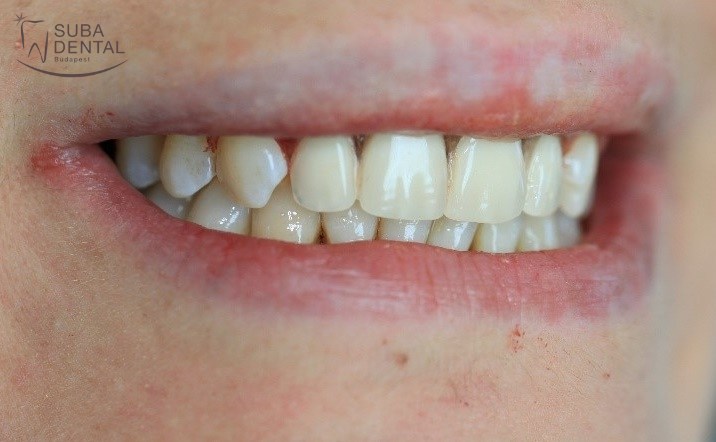

Az koronák végleges ragasztása után páciensünk újra boldogan tud mosolyogni, nem kell többé takargatnia a fogait.

Előtte

Utána